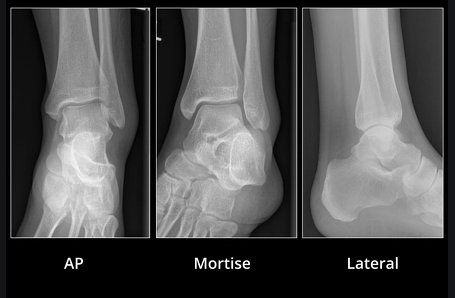

Ankle injuries, particularly ankle sprains are among the most common injuries seen by sports physiotherapists. Especially on the